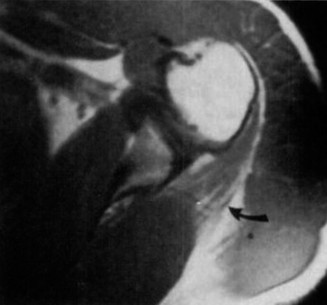

You send the patient for an MRI, which is shown in Figure 2–66.

Figure 2–66

The correct answer is (C). The patient’s clinical examination findings of isolated

weakness in external rotation and atrophy of the infraspinatus muscle point to suprascapular nerve entrapment at a location past the exit point for the branch to the supraspinatus muscle. Also, MRI reveals a posterior labral tear with a paralabral cyst that is compressing the suprascapular nerve at the spinoglenoid notch. Choice A, while fitting with the patient’s clinical examination, does not fit with the MRI showing paralabral cyst. Choices B and D are incorrect because entrapment of the suprascapular nerve at the suprascapular notch by scapular body fracture or by the transverse scapular ligament (more common) would lead to weakness/atrophy in both supraspinatus and infraspinatus muscles as the suprascapular notch is proximal to the nerve branch point to the supraspinatus muscle.